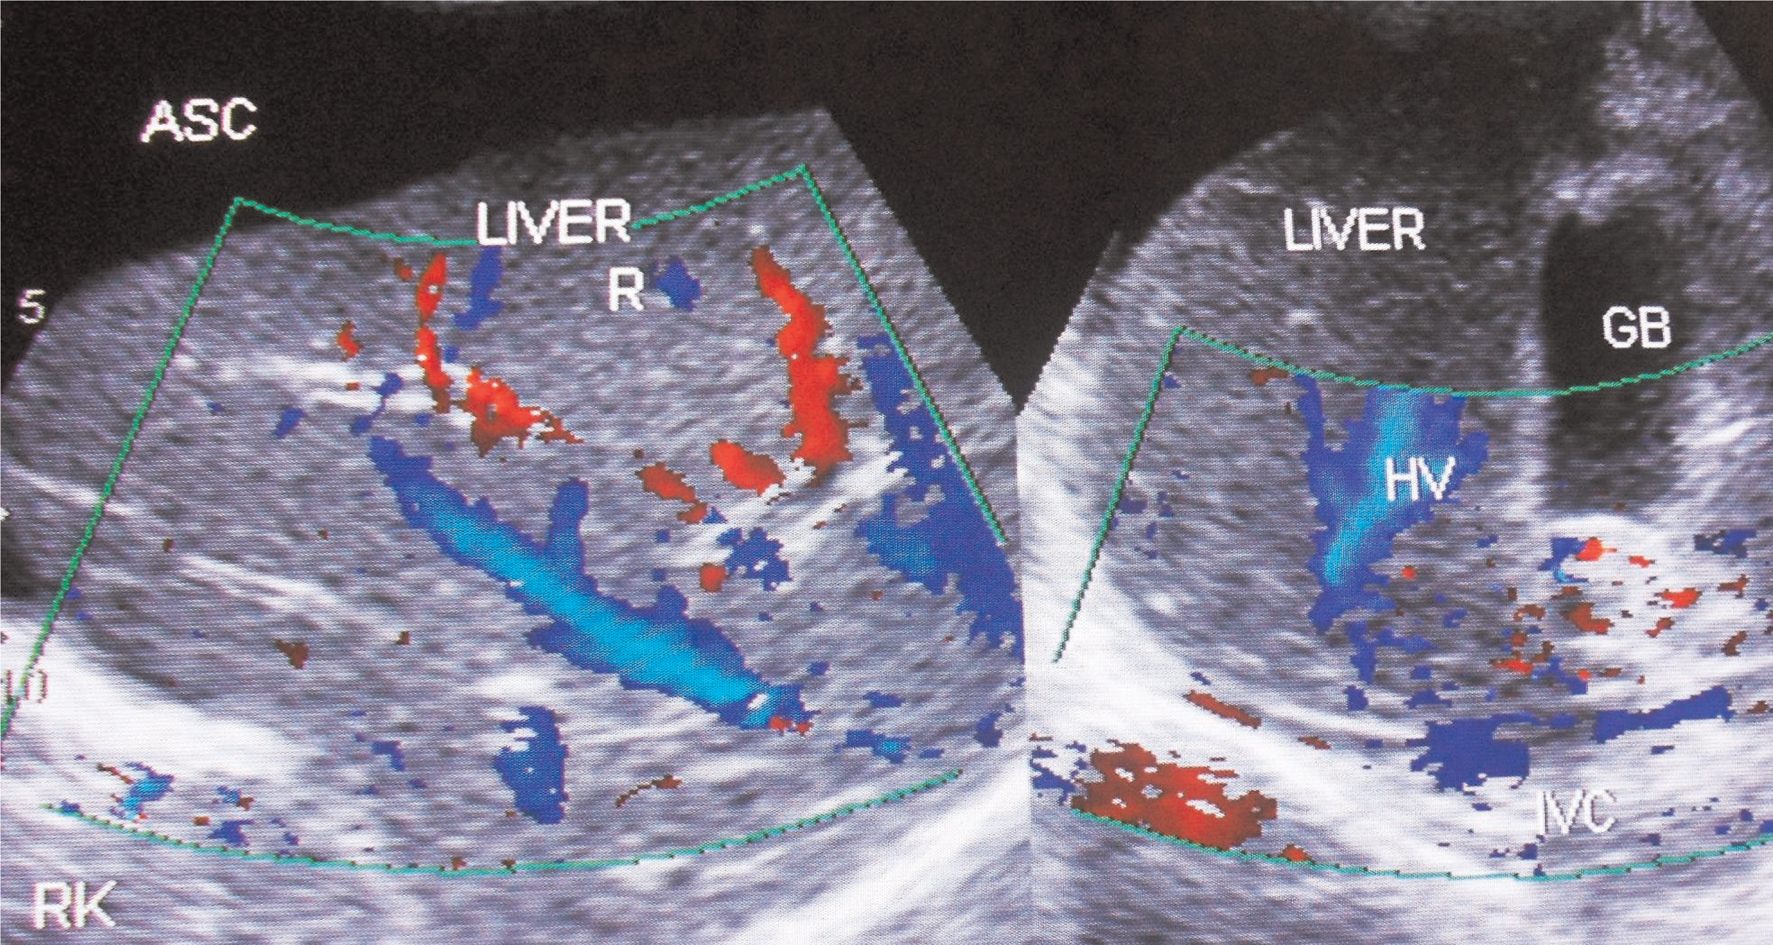

Fig 6

Figure 6. Ultrasonography and color Doppler of a patient with ascites due to HVCS. IVC shows stenosis at cavo-atrial junction with distal segment dilated. IVC is filled with organized thrombus. There is obstruction to blood flow at the hepatic vein outlets. Note thrombosis of medium-sized tributaries of right hepatic vein. GB, gall bladder; HV, hepatic vein; RHV, right hepatic vein. (Copyright: Santosh Man Shrestha).